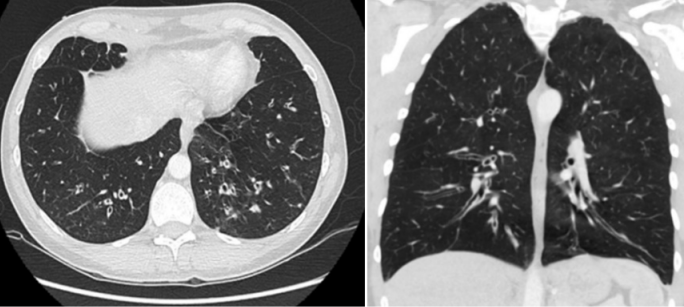

除了感染性疾病外,PID患者也经常出现呼吸系统过敏性疾病。2018年Lyons和Milner提出了PAD(primary atopic disorders,原发性特应性疾病)这一术语,旨在描述表现为过敏反应的遗传性单基因疾病[15]。遗传关联研究支持“几种引起PAD的突变基因均可导致相同的过敏性疾病”这一假说[16]。例如CARMIL2(RLTPR)缺陷通过减少IFN-γ、TNF、IL-17A/F及IL-22的水平影响T细胞的功能[17],而CARD14缺陷降低了NF-κB信号通路活性及皮肤特定种类抗菌肽的产生[18]。上述这两种基因缺陷的部分患者最终都可出现支气管哮喘(简称哮喘)[17]。Bjelac等[19]在一项包含160例患者的CVID回顾性队列研究中,发现相当比例的CVID患者合并哮喘(60例,37.5%)、过敏性鼻炎(89例)、食物过敏(18例)、青霉素过敏(34例)等IgE介导的过敏性疾病,但哮喘患者中仅10%发现过敏原。由于CVID和哮喘均可以表现为长期咳嗽、咳痰、甚至支气管扩张,导致CVID的诊断相当具有挑战性。Ibrahim等[20]报道的1例诊断为“哮喘”患者(图1),免疫球蛋白水平极低(IgG、IgM和IgA)、无明显T细胞缺陷/免疫球蛋白缺陷及获得性免疫缺陷等证据,支持CVID的诊断。

图片

图1  CVID合并哮喘的患者肺部CT:弥漫性气道增厚和支气管扩张,小气道黏液嵌塞,伴远端小叶中心性结节[20]

图片来源:Recurrent asthma exacerbations: co-existing asthma and common variable immunodeficiency (DOI: 10.1080/02770903.2021.1922913)